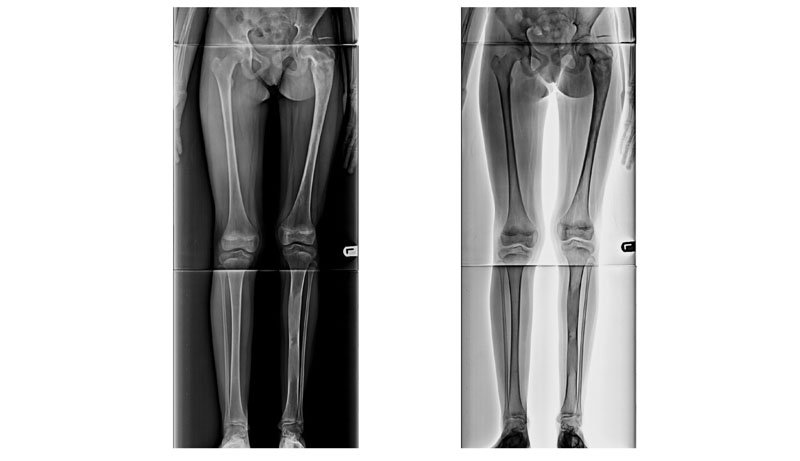

Full Length X-Ray

Indications

1 : For planning of any realignment operation of lower limb, mainly for genu valgus & varus deformity due to osteoarthritis / post # healing.

2 : To measure limb length discrepancy - congenital/acquired.